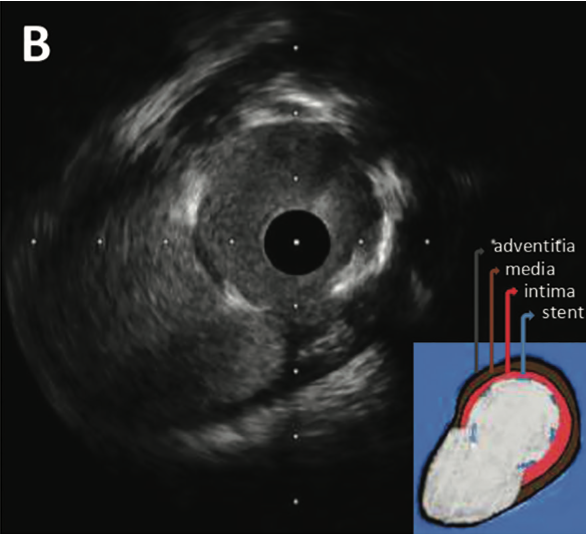

Intravascular ultrasound (IVUS) and optical coherence tomography (OCT) visualized a defect in the coronary vascular wall with interrupted intima and internal elastic membrane at the perforated site (Figure 1B and Figure 1C).